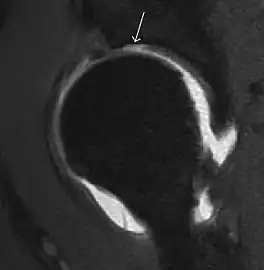

Most of the angles and measurements described in the plain radiograph section can be accurately reproduced on MRI. In addition, the superiority of MRI resolution with intra-articular contrast allows detection of labral and chondral abnormalities that may influence the choice of medical, percutaneous, or surgical management (Figure 9).[1]

Figure 9:

Coronal CT-arthrography (d) showing ligamentum teres tear.[1]

MR arthrography can also demonstrate ligamentum teres rupture or capsular laxity, which are debated causes of microinstability of the hip. Elongation of the capsule or injury to the iliofemoral ligament or labrum may be secondary to microtrauma in athletes. MR can demonstrate abnormalities in these cases, such as increased joint volume or a ligamentum teres tear (Figure 9).[1]